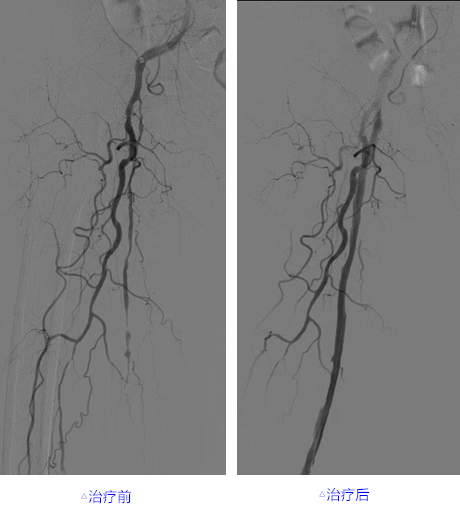

再次造影评估,闭塞段血管复通,血流重现生机,随后使用直径由小到大的普通球囊序贯扩张血管,介导药涂球囊到达原来闭塞的血管段再次扩张,使其表面的药物精准贴附血管壁,抑制血管内膜的增生,进一步巩固疗效。台上检查患者的右足,足趾的颜色由紫绀转为红润,皮温转暖,标志着手术成功。